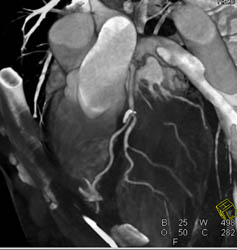

Normal Coronary Artery Anatomy